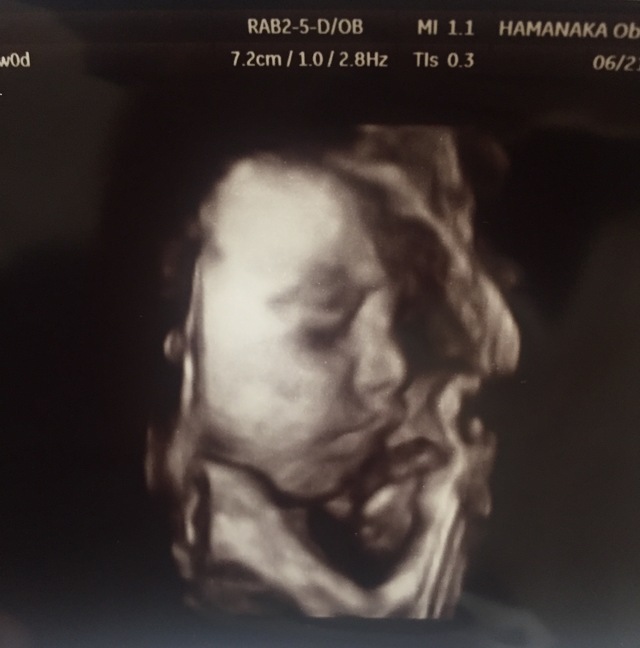

24週0日(24w0d・女の子)|ゆっちゃんちゃん さん(32歳)

エコー写真撮影時のエピソード:

前回の健診では、顔を手で隠していて見せてくれなかったけれど、この健診では顔をはっきり見せてくれてうれしかったです。

またこの次の健診では顔を隠していました。 なかなかはっきり見せてくれるときが少ないです。